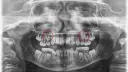

W przypadku nagłych problemów stomatologicznych, takich jak silny ból zęba, urazy jamy ustnej czy powikłania po leczeniu stomatologicznym, pacjenci mogą skorzystać z dyżurów stomatologicznych. Te usługi są dostępne w dni powszednie od 19:00 do 7:00 następnego dnia oraz całodobowo w weekendy i dni wolne od pracy. Warto wiedzieć, że te placówki obsługują wyłącznie pacjentów w nagłych przypadkach, co oznacza, że można uzyskać pomoc bez wcześniejszej rejestracji.

- Ból zęba, który nie ustępuje

- Urządzenie zęba lub złamanie zęba

- Infekcje jamy ustnej

- Powikłania po leczeniu stomatologicznym